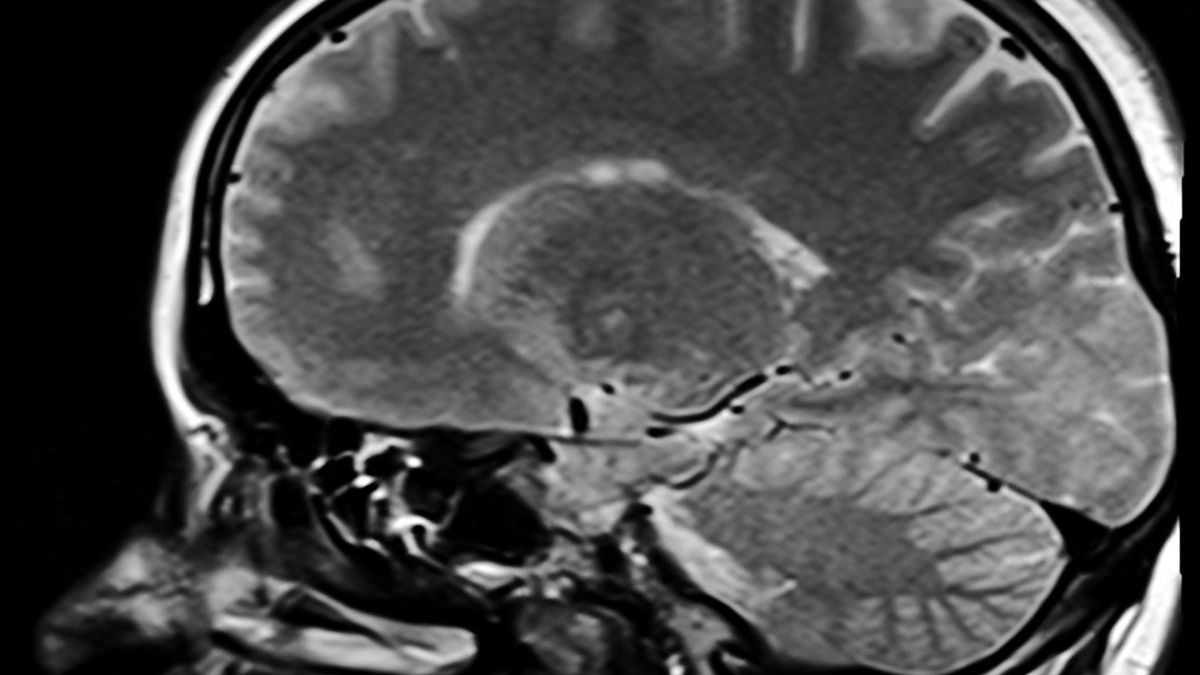

Na potrzeby najnowszych badań porównano ilość istoty białej u chorujących dyplomatów z jej ilością u zdrowych ochotników. U dyplomatów jej ilość wynosiła średnio 542 cm3, u ochotników było to 569 cm3. Ponadto amerykańscy dygnitarze mieli znacznie słabszą sieć połączeń w obszarach mózgu odpowiedzialnych za przetwarzanie dźwięków i obrazów.